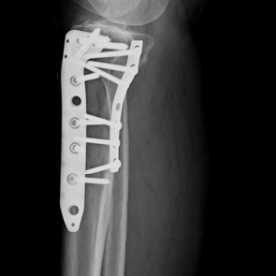

Röntgenbilder